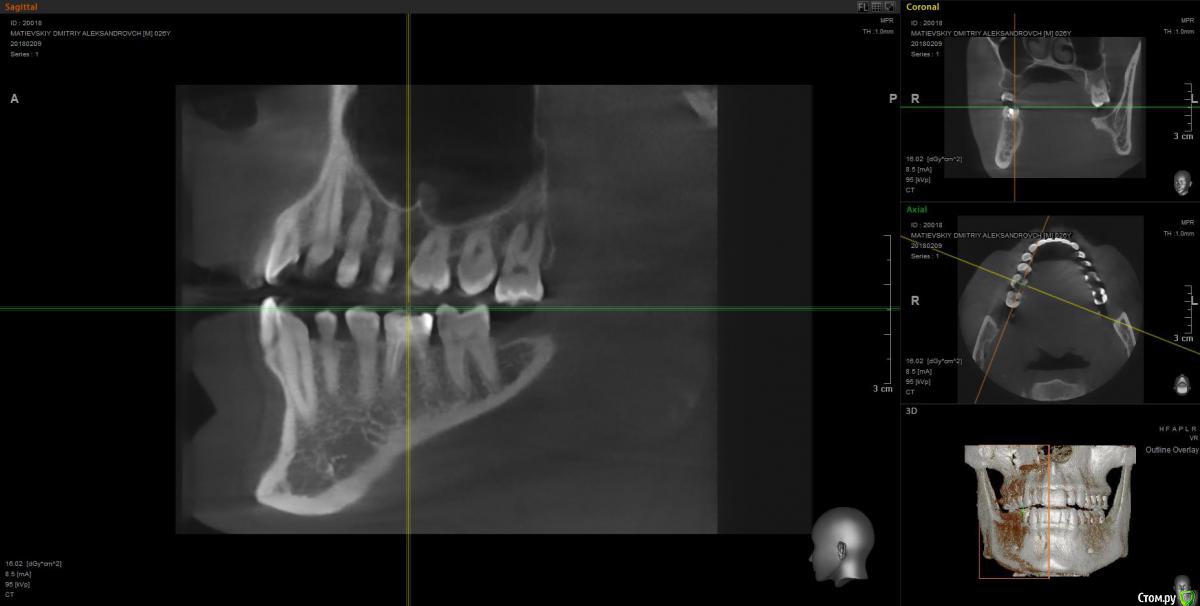

Dmitry91 Опубликовано 13 февраля, 2018 Поделиться Опубликовано 13 февраля, 2018 Добрый день, уважаемые доктора и знатоки! Прошу вашей помощи или мнения по ситуации. Есть проблемный 6й зуб на правой нижней челюсти с огромной пломбой на штифте.Внизу у корней круглые образования (кисты). Под пломбой, похоже, кариес. Стоит ли удалять зуби ставить имплант? Или есть возможность сохранить зуб? Что посоветуете? Если имплант, то какой лучше? Второй вопрос. Нужно ли удалять верхние зубы мудрости (нижних нет)? Похоже рядом с ними на 7ках естьконтактный кариес из-за того, что между зубами мудрости и 7ками застревает пища. Приложил скрины КТ и само 3D КТ в архиве, ссылка ниже. https://yadi.sk/d/kfX43ds43SMxCo Если нужно посмотреть фото с другой стороны, могу сделать. Кто поможет, заранее спасибо!) Ссылка на комментарий

Irouil Опубликовано 13 февраля, 2018 Поделиться Опубликовано 13 февраля, 2018 Удалять восьмерку (вижу только одну) - ОБЯЗАТЕЛЬНО! Удалять шестёрку? Я перспективы лечения не вижу. Какой имплант ставить? Самый надёжный, без оглядки на эстетику. Ссылка на комментарий

DmitrySH Опубликовано 13 февраля, 2018 Поделиться Опубликовано 13 февраля, 2018 ? Или есть возможность сохранить зуб? Если хотите гарантий, то удаляйтеЕсли есть желание сохранить зуб, то можно перелечить. Очаги воспаления скорее всего пройдут, но зуб будет достаточно хрупкий и ненадежный. Соответственно без гарантии. А по стоимости примерно равносильно имплантации Ссылка на комментарий

колесников Опубликовано 14 февраля, 2018 Поделиться Опубликовано 14 февраля, 2018 6ка удаляется. Желательно одномоментно поставить Имплант. Рекомендую Astra tech. Из дополнительных манипуляций будут:формирователь,0,5г костного материала, пластика десны. Верхняя восьмерка ,с этой стороны , так же удаляется. Ссылка на комментарий